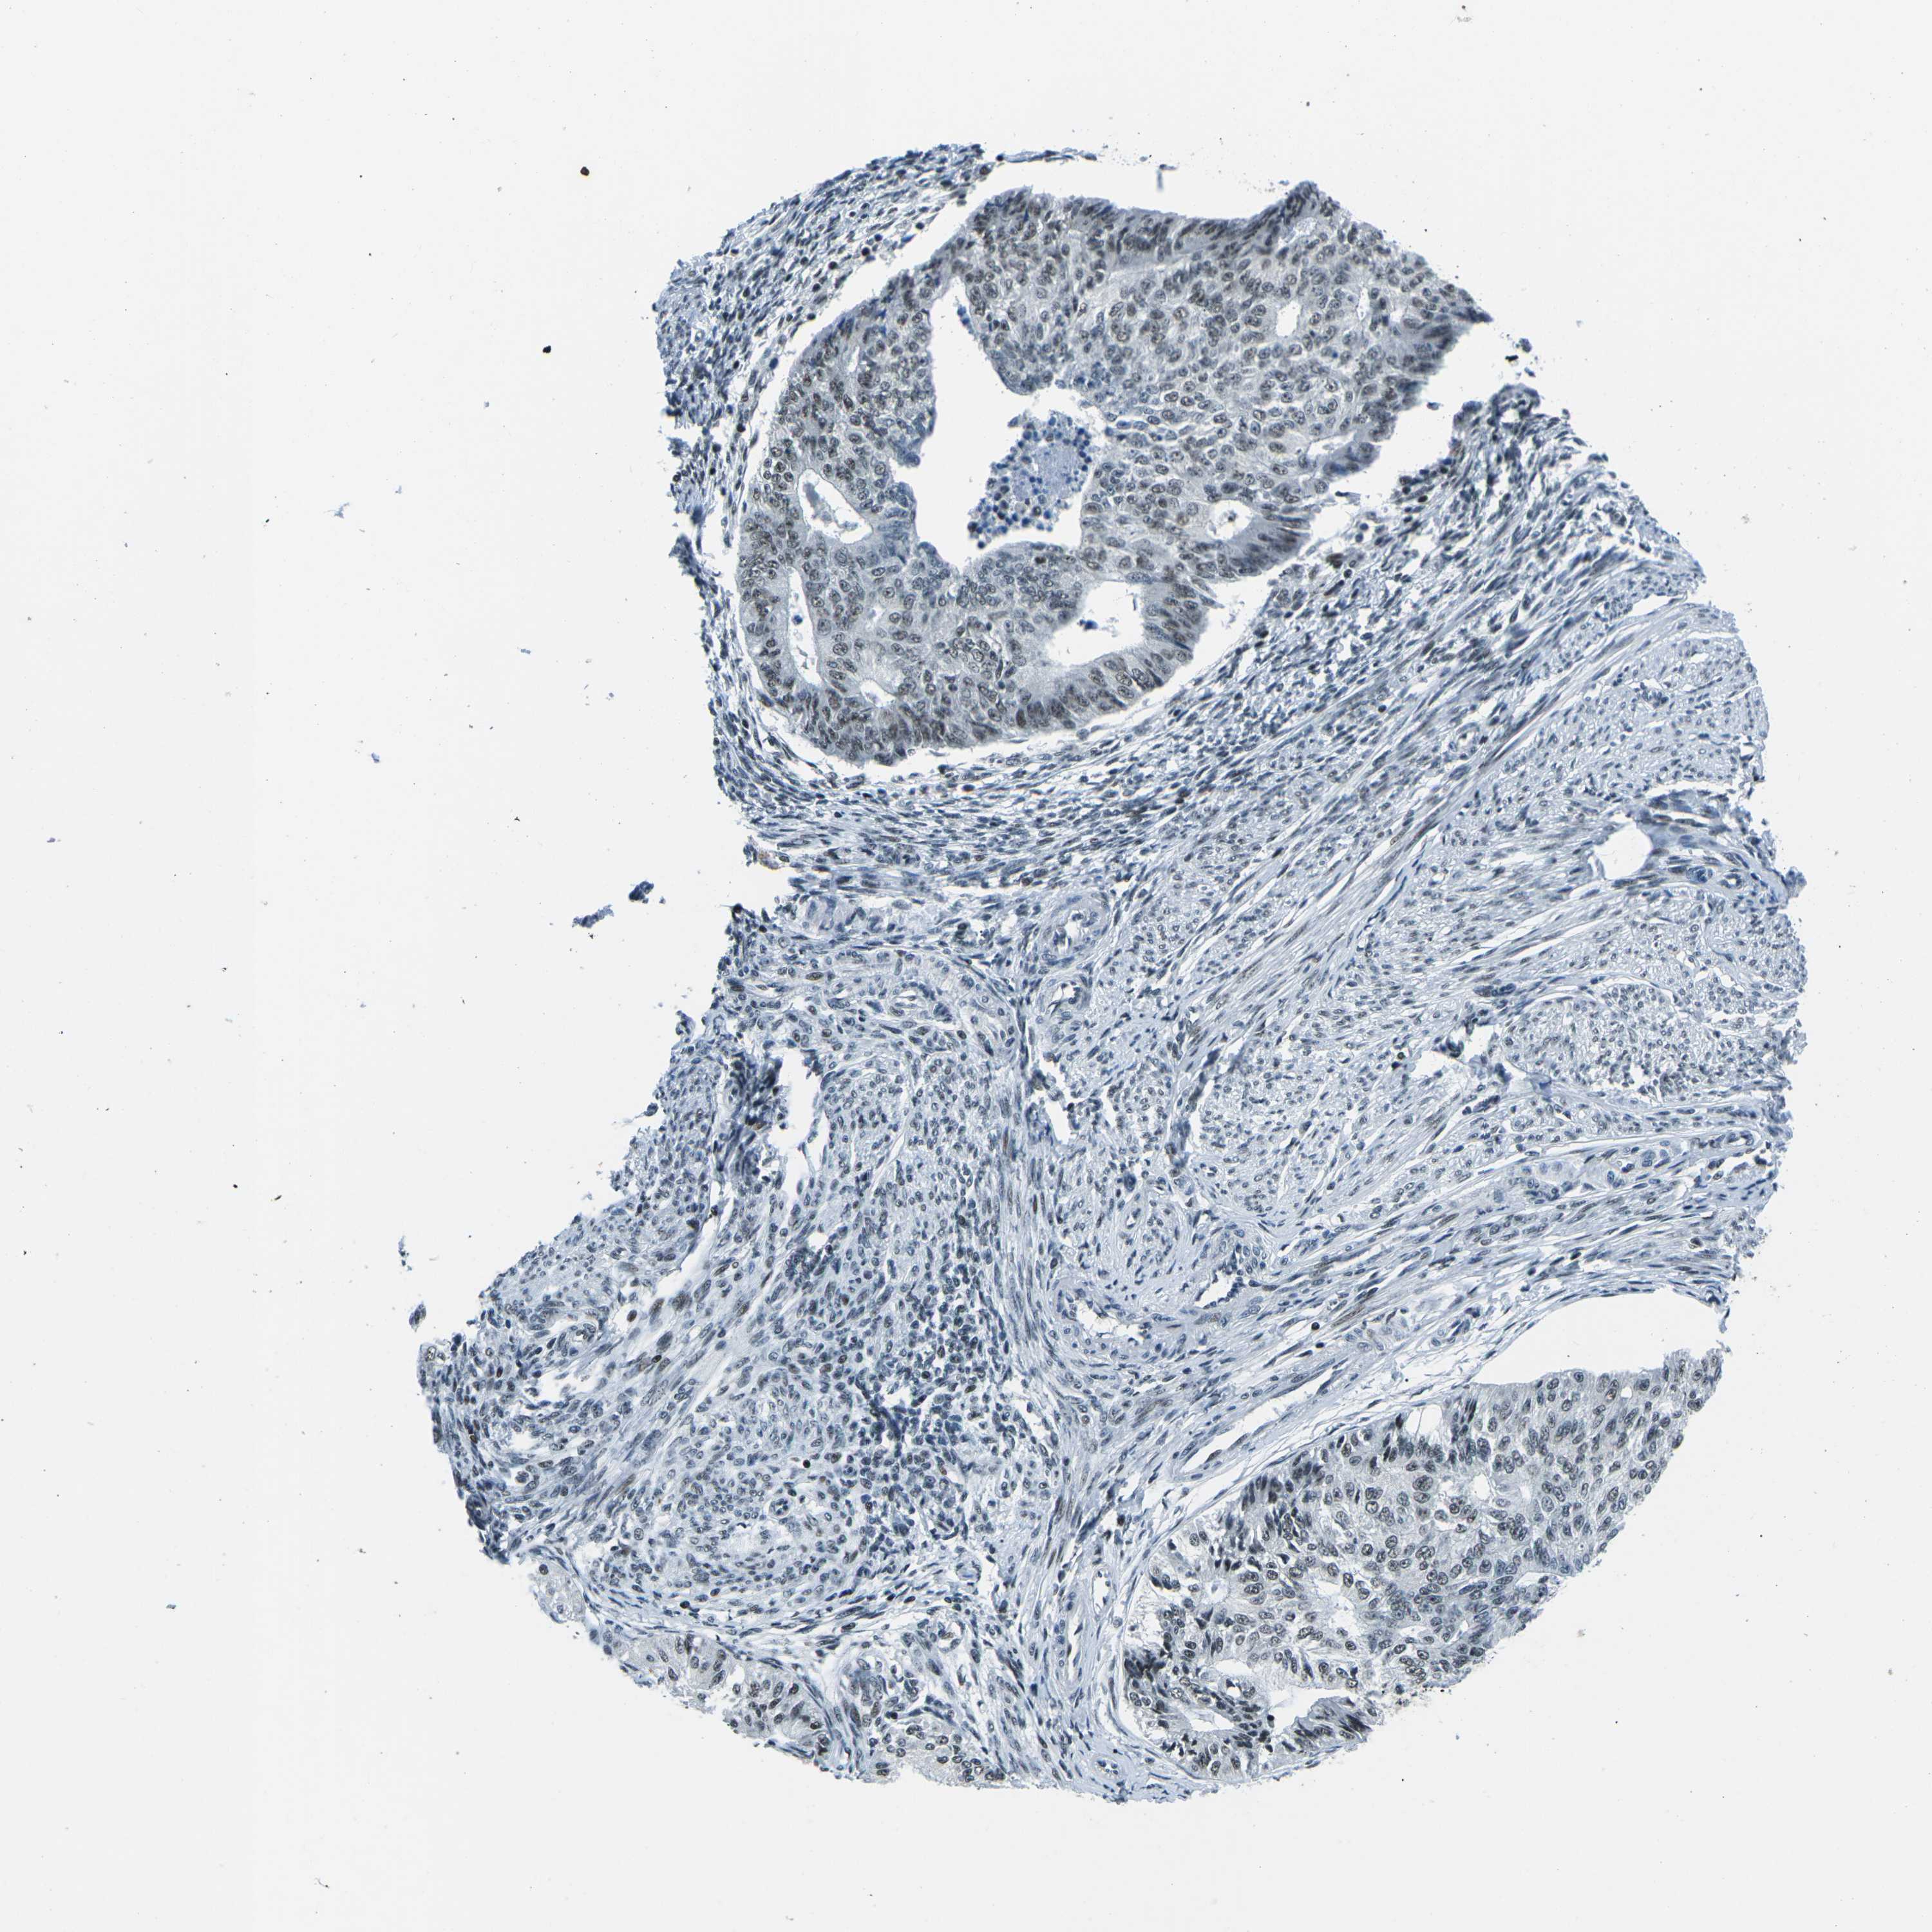

ENDOMETRIAL CANCER - Protein expressioni

A mouse-over function shows sample information and annotation data. Click on an image to view it in a full screen mode. Samples can be filtered based on level of antibody staining by selecting one or several of the following categories: high, medium, low and not detected. The assay and annotation is described here.

Note that samples used for immunohistochemistry by the Human Protein Atlas do not correspond to samples in the TCGA dataset.

Antibody stainingi

Antibody staining in the annotated cell types in the current human tissue is reported as not detected, low, medium, or high, based on conventional immunohistochemistry profiling in selected tissues. This score is based on the combination of the staining intensity and fraction of stained cells.

Each image is clickable and will lead to virtual microscopy that enables deeper exploration of all samples and also displays staining intensity scores, fraction scores and subcellular localization as well as patient and tissue information for each sample.

Antibody HPA019703

Antibody CAB016547

Staining

High

Medium

Low

Not detected

Intensity

Strong

Moderate

Weak

Negative

Quantity

>75%

75%-25%

<25%

None

Location

Nuclear

Cytoplasmic/membranous

Cytoplasmic/membranous,nuclear

Adenocarcinoma, NOS

Adenoma, NOS